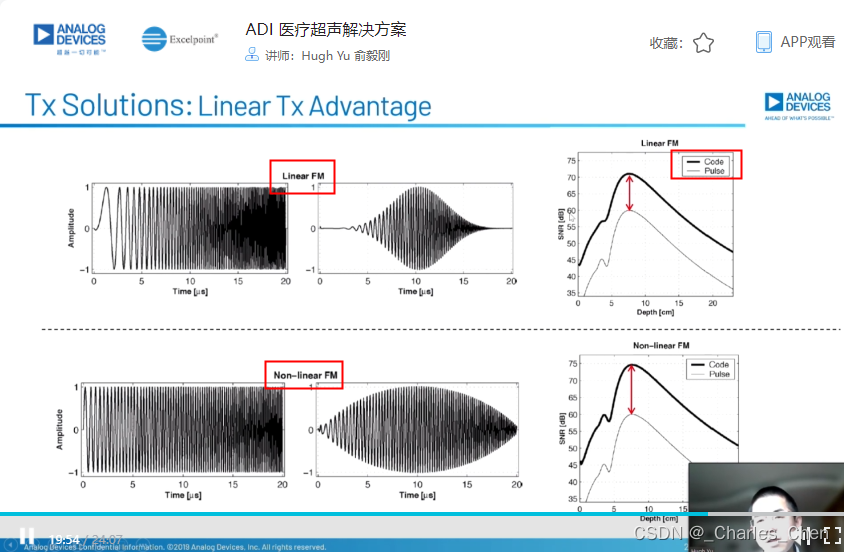

数字发射波束成形器用于产生所要求的数字发射信号,以正确的时间和相位生成聚焦发射信号。高性能超声系统可通过任意波形发生器产生复杂的发射波形,从而优化图像质量。这些情况下,发射波束成形器以大约40MHz速率生成8位至10位数字字符,并以此产生所要求的发射波形。数/模转换器(DAC)将数字波形转换成模拟信号,通过线性高压放大器进行放大,用于驱动传感器单元。由于这种发射技术占用较大体积,而且价格昂贵、需要消耗较高能量,所以,这种架构只限于昂贵的非便携设备。多数超声系统并不使用这种发射波束成形技术,而是采用多级高压脉冲发生器产生需要发射的信号。在这种替代方案中,利用高集成度、高压脉冲发生器快速切换传感器单元至适当的可编程高压电源,产生发射波形。为了产生一个简单的两极发射波形,脉冲发生器需要交替地将传感器单元切换到由数字波束成形器控制的正、负发射电压。更复杂的设计可以让传感器单元切换至多路电源和地,从而产生更复杂、性能更好的多重波形。